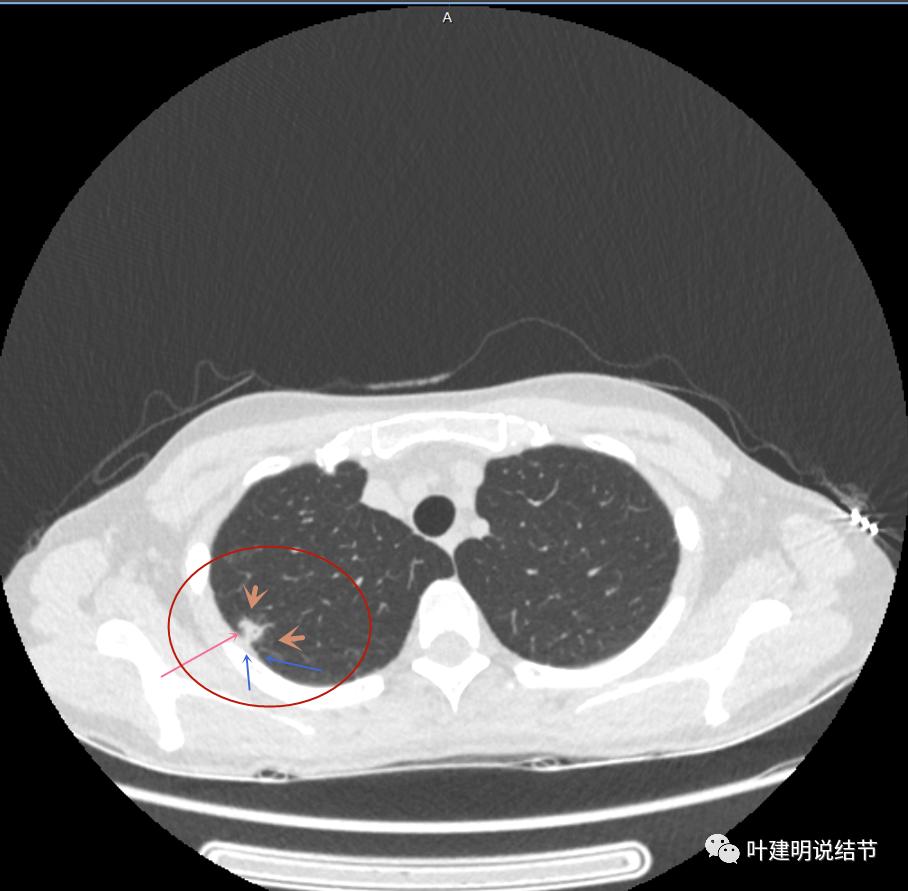

上面是她提供的病史资料,其中最重要的是PPD强阳性!其他主要看影像,我们先来看她2020年7月份的平扫片子(由于片子较多,详细展示是为了同道分析,我在影像特征描述上将只选取部分加以说明):

右肺尖偏实性结节(粉色箭头),邻近胸胸膜明显增厚不平,且广基附在胸壁上(蓝色箭头)

有卫星病灶(绿色箭头)

胸壁侧病灶较厚,模糊(蓝色箭头),仍见卫星灶(绿色箭头)

主病灶出现,粉色箭头示病灶密度较高,边上有磨玻璃影,甚淡(砖色箭头)

病灶有空洞(黄色箭头),主病灶边上见条索状高密度影(细红色箭头),邻近胸膜有粘连(蓝色箭头)